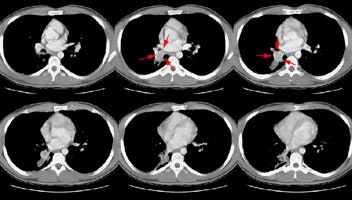

A CT scan of the chest was performed and revealed a heterogeneous soft tissue mass in the right interlobar bronchus with post-obstructive atelectasis.